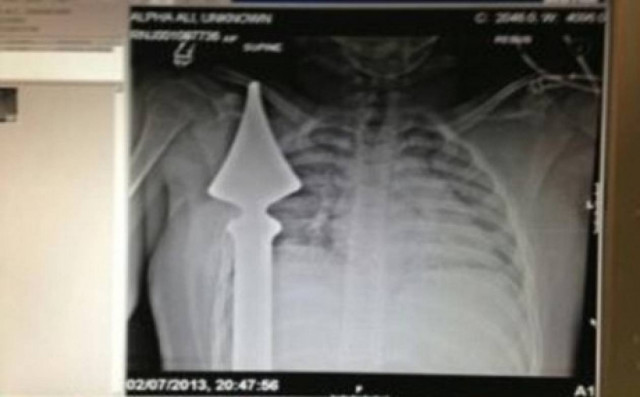

Ζει από θαύμα: Μαθητής καρφώθηκε σε μεταλλικό φράχτη

Από του Χάρου τα δόντια γλίτωσε ένα αγόρι 12 ετών, όταν καρφώθηκε επάνω σε μεταλλικό φράχτη ενώ έπαιζε κοντά στο σπίτι του στο Essex.

Ο Josh Hassan έχασε την ισορροπία του ενώ προσπαθούσε να πιάσει τη μπάλα του, όπως είπε στη Daily Mail, και βρέθηκε με ένα σίδερο καρφωμένο στην περιοχή του στήθους, μερικά εκατοστά μακριά από την καρδιά του.

Τις απεγνωσμένες κραυγές του άκουσε η μητέρα του, η οποία σοκαρισμένη από το θέαμα του παιδιού της που αιμορραγούσε, προσπάθησε μαζί με δύο γείτονές της να συγκρατήσουν το σώμα του παιδιού, για να μην μπει πιο βαθιά το σίδερο στο σώμα του